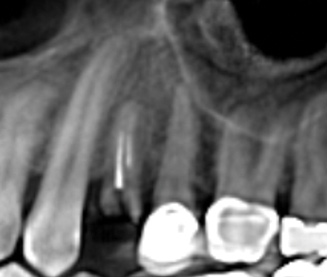

(4.) Digital plan of the virtual implant.

Figure 4

(5.) Digital plan of the virtual implant.

Figure 5

After a CBCT scan (Figure 3) and a digital impression were obtained for diagnosis and treatment planning, the DICOM file from the CBCT scan and the STL file from the digital impression were merged in a treatment planning software application for evaluation. A virtual crown was then created to facilitate a restoration-driven approach. The vital structures and osseous anatomy were identified, and the implant position was planned virtually (Figure 4 and Figure 5).